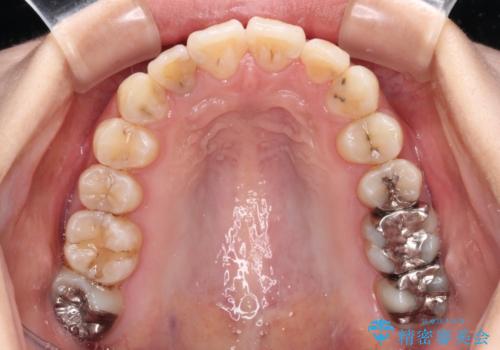

- 虫歯が多く、磨きにくい歯並びを改善したいとのことで来院された患者様です。

歯列は叢生が認められる程度でしたが、やや前突感があったので、少しでも口が閉じやすくなるように仕上げる方針としました。

神経を取り除かれている歯3本以外にも虫歯が認められたため、事前に処置を行い、インビザラインにて矯正治療を行うこととしました。

神経が取り除かれている歯は、クラウンによる補綴治療が必要であるため、矯正治療後にオールセラミッククラウンにて補綴治療を行うこととしました。

歯磨きしやすくなるとともに、飛び出していた前歯も引っ込めて整えることができました。